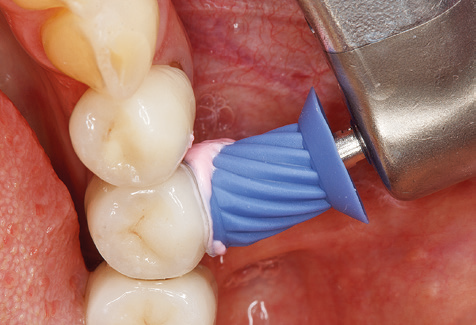

Die gute Ausleuchtung des Arbeitsfeldes stellt eine wesentliche Erleichterung dar. Bei dem von den Autoren genutzten System ist dies gelungen, indem ein 5­facher LED­Ring in das Handstück integriert wurde. Natürlich werden für dieses System unterschiedliche Arbeitsspitzen für die jeweiligen Indikationsbereiche angeboten. Eine gerade, universell einsetzbare Spitze ist das Basisinstrument zur maschinellen Instrumentierung natürlicher Zähne (Abb. 5a und b). Für schwer zugängliche Bereiche im Seitenzahnbereich werden gebogene Spitzen angeboten, die auch einen Zugang zu freiliegenden Furkationen ermöglichen (Abb. 6).

Unerlässlich für die UPT implantat­ prothetisch versorgter Patienten sind natürlich Arbeitsspitzen für die Reini­gung von Implantatoberflächen. Der Implantatreinigungsaufsatz des hier verwendeten Systems zeichnet sich dabei durch eine spitz zulaufende sechskantige konische Form aus. Dieses Design erlaubt ein leichtes atraumatisches Eindringen in die periimplantäre Tasche und zeigt eine gute Reinigungsleistung (Abb. 7).

Abb. 4: Für das Sondieren an dentalen Implantaten sind biegsame, millimeterskalierte Sonden empfehlenswert (z.B. Colorvue Kit PCV11KIT6, Hu-Friedy). – Abb. 5a und b: Eine gerade Arbeitsspitze (1P, W&H Dentalwerk Bürmoos GmbH) ist universell für die Instrumentierung natürlicher Zähne geeignet. – Abb. 6: Für die Bearbeitung schwer zugänglicher Bereiche der Zahn- und Wurzeloberflächen (z.B. Furkationen) bieten sich gebogene Arbeitsspitzen (3Pr/3Pl, W&H Dentalwerk Bürmoos GmbH) an. – Abb. 7: Die spitz zulaufende sechseckige Implantatreinigungsspitze (1I, W&H Dentalwerk Bürmoos GmbH) ermöglicht eine atraumatische und effiziente Reinigung der Kronen- und Abutmentoberflächen. – Abb. 8: Für die manuelle Instrumentierung der Implantatoberflächen sind Titan- oder Carbonküretten geeignet.